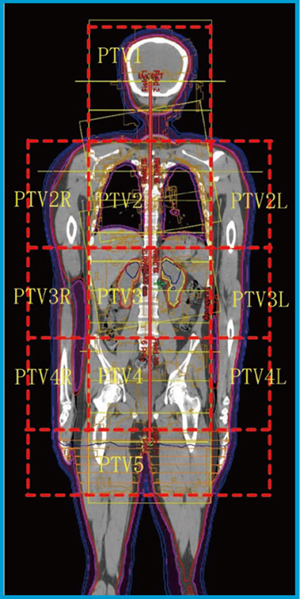

2プランの接合部はセットアップエラーによる過線量を考慮して大腿部とした。治療計画はbodyの輪郭描出後,体表から3mm内側の領域でorgan at risk(OAR)を3~5mmマージンで切り取ったものをplanning target volume(PTV)とした。水晶体,肺,腎臓をOARとした。全身各部位に効果的な最適化指示を行うため,頭部~体幹部領域は図1のように20~24cm間隔でPTVをPTV1~5と5分割,さらに,PTV2~4は正中,右端,左端と3分割した。プラン接合部のPTV5は,2cmごとに7分割した。下肢領域のPTVも大腿のプラン接合部,足指部分,それ以外と3分割し,大腿のプラン接合部はPTV5と同様に7分割した。

図1 症例1の治療計画 |